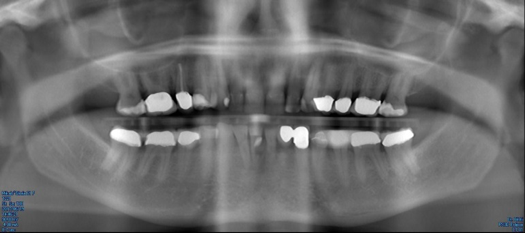

Fig 29. Preoperative Panorex.

Figure 29

The next case follows the digital protocol for fully guided surgery and prosthetics. A CBCT radiograph, digital impression, and digital photography were the cornerstones to the success of this case. The 3D data set was electronically delivered to the dental laboratory. The data were merged and the process to develop the plan was initiated. The use of CBCT was essential in this case, particularly due to minimal space for placement of individual implants and single-unit crowns. The patient's chief concern was that she wanted to have single-unit crowns instead of fixed crown-and-bridge restorations because she was worried that she would someday find herself in an assisted-living facility; if that were to happen, she wondered, who would help floss under her bridge work? Her decision was to have single implants with individual crowns. CBCT technology is much more accurate in evaluating space maintenance and management.10 Periapicals in the past were rather close for calculating spacing; however, the CBCT identifies the buccal-lingual dimensions as well as the mesial-distal measurements. On review of the completed proposals for implant placement and provisionals, it was determined that there was sufficient spacing for implant placement to allow appropriate emergence profiles for the provisionals and then eventually the final single-unit cemented crowns. The proposal was accepted, and a 3D-printed surgical stent was fabricated, along with the PMMA provisionals (Figure 29 through Figure 35).